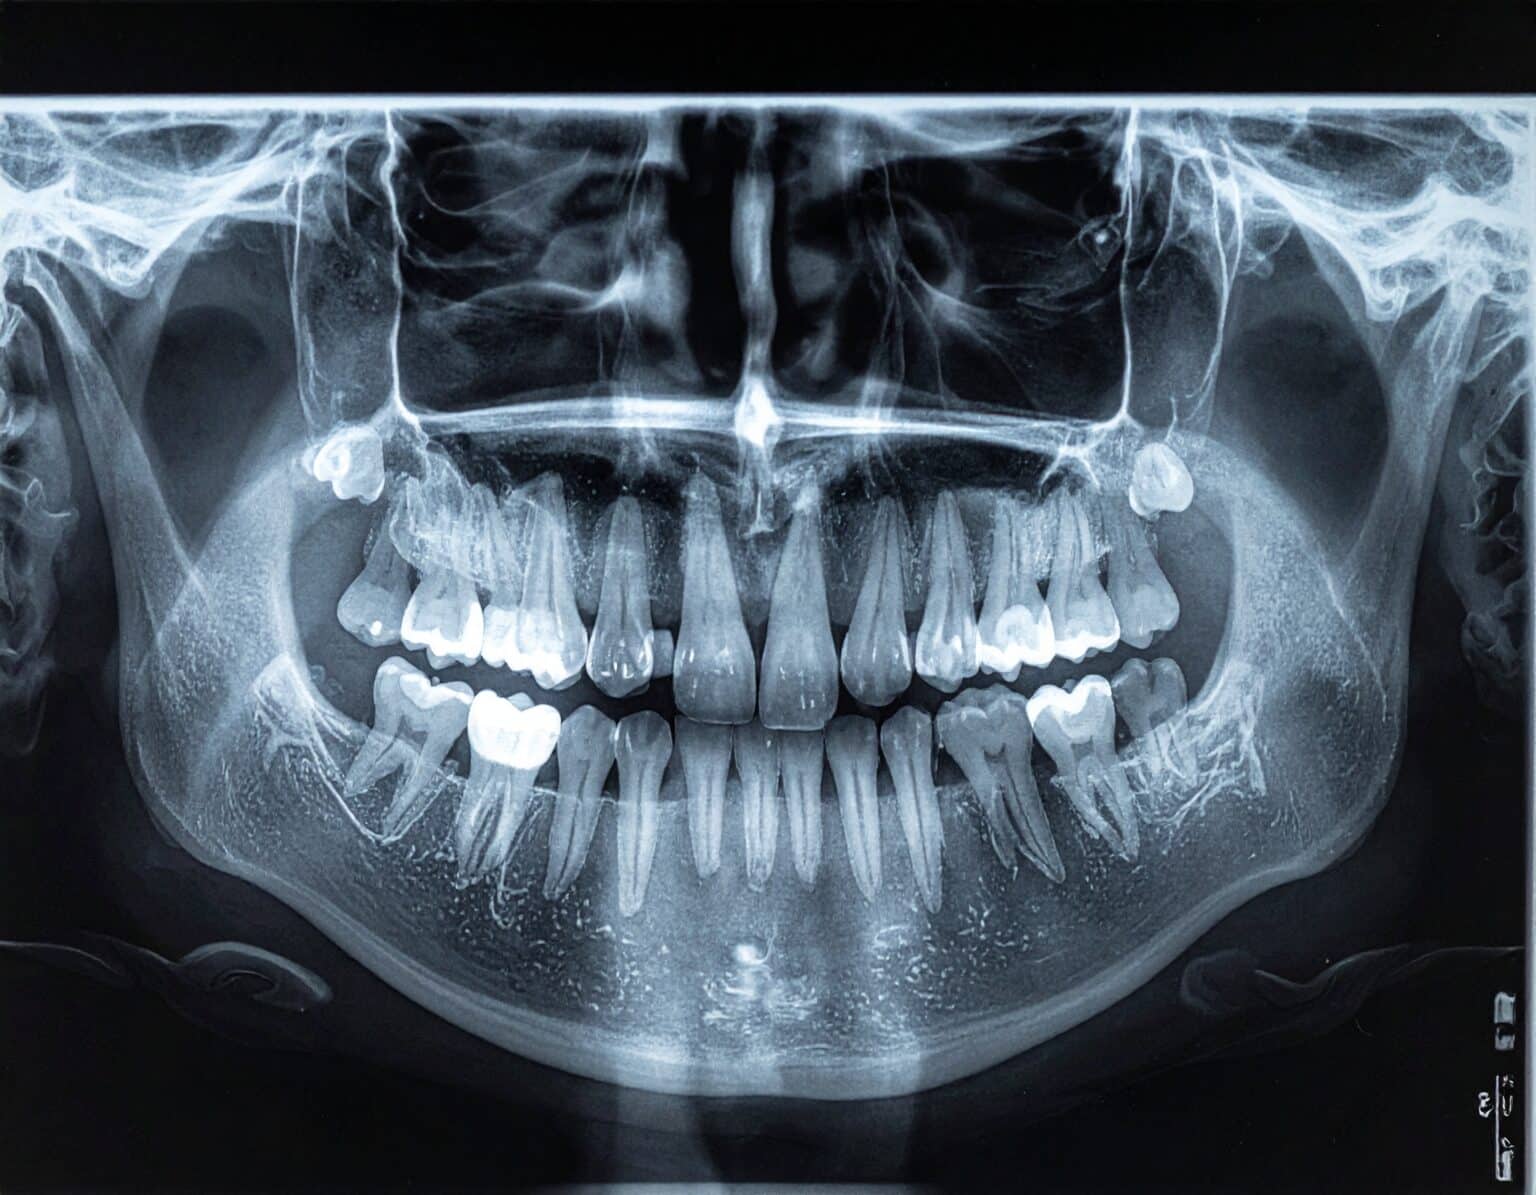

Overjet’s artificial intelligence technology transforms traditional black-and-white X-rays by adding a layer of data that instantly outlines decay (cavities) and measures bone loss. This makes it easy for you to see your results alongside your dentist.

One of the reasons we added Overjet is because it makes it much easier for you to see what your doctor sees. We know it can be hard for patients to interpret a traditional black-and-white X-ray. Overjet’s artificial intelligence technology highlights the X-ray to draw the eye to areas of concern. It also highlights past dental work that’s been completed, such as fillings, crowns, and root canals. One of the reasons we added Overjet is because it makes it much easier for you to see what your doctor sees. We know it can be hard for patients to interpret a traditional black-and-white X-ray. Overjet’s artificial intelligence technology highlights the X-ray to draw the eye to areas of concern. It also highlights past dental work that’s been completed, such as fillings, crowns, and root canals.

The AI algorithms identify cavities, both large and small. We like to catch cavities when they are small! Bone loss is often a sign of periodontal disease, a common gum infection that causes the jawbone and tissue supporting the teeth to deteriorate if not treated. Overjet quantifies the level of bone supporting each tooth and lists the measurement level right on the X-ray. That, combined with your dental examination, will let you know how healthy your gums are. After all, your gums are the foundation for your teeth.